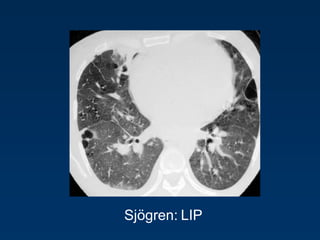

Benign lymphoproliferative

disorder

Diffuse interstitial infiltration of

mononuclear cells

Not limited to the air ways as

in follicular Bronchiolitis

LIP

= Lymphocytic Interstitial Pneumonia

Sjögren: LIP

Rarely idiopathic

In association with:

Sjögren‟s syndrome

Immune deficiency syndromes, AIDS

Primary biliary cirrhosis

Multicentric Castlemean‟s disease

Sjoegren disease